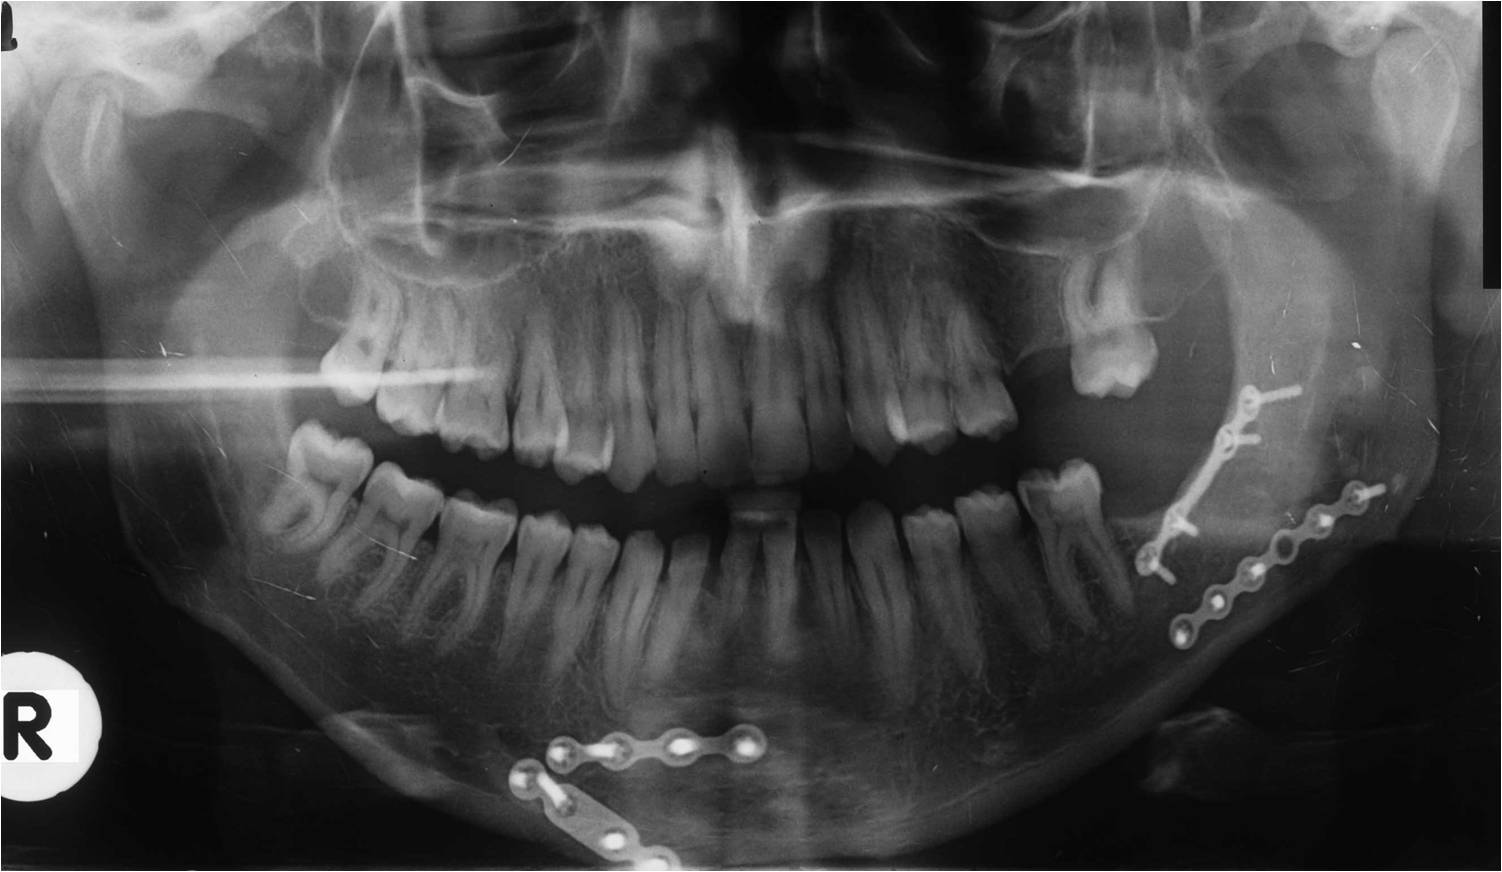

Ο γναθοπροσωπικός χειρουργός έχει, λοιπόν, πλατιά εκπαίδευση στην αντιμετώπιση τραυματικών κακώσεων του προσώπου, όπως είναι τα κατάγματα της άνω και κάτω γνάθου, του οφθαλμικού κόγχου, των ζυγωματικών οστών, του μετωπιαίου οστού και του ρινοηθμοειδικού συμπλέγματος, καθώς και των θλαστικών κακώσεων των μαλακών μορίων του προσώπου (Εικόνα 31Α, 31Β, 31Γ).